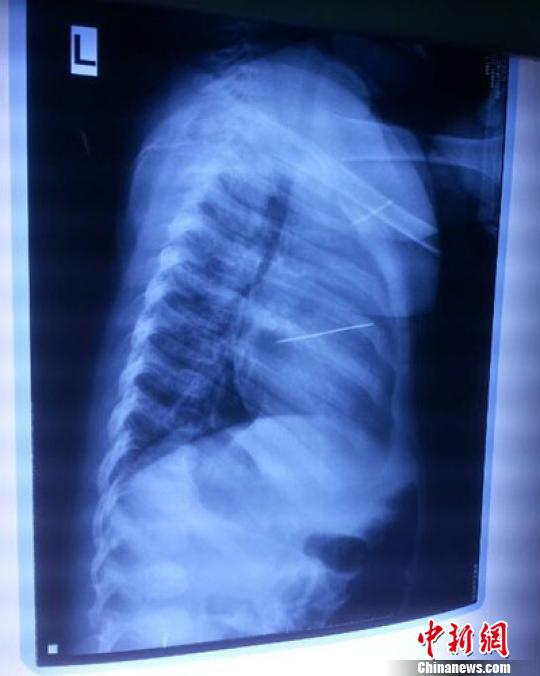

女嬰胸片提示心臟里面扎了一個縫衣針 蔡迅翔 攝

醫(yī)院胸心外科主任翟波介紹說,1月22日,小患者彤彤因?yàn)榘l(fā)燒抽搐來醫(yī)院就診,常規(guī)檢查時發(fā)現(xiàn)孩子心臟里面扎了一個縫衣針。

“第二天上午,我們做了個緊急彩超檢查,發(fā)現(xiàn)針是從患者右心室表面刺入,穿破室間隔,到達(dá)左心房,中間還有一部分損害到二尖瓣。于23號下午,我們就做了一個緊急手術(shù),手術(shù)中發(fā)現(xiàn),這枚針已經(jīng)刺入心臟,沒入了右心室的下面,表面已經(jīng)看不到針了,僅能看到一個小針眼,還在往外滲血,一點(diǎn)一點(diǎn)的滲,心包腔里面大概有100多毫升的出血,心包上一個洞,針在右心室表面刺入以后,穿過室間隔,在二尖瓣的上方,進(jìn)入了左心房,在針的四周,有很多纖維沉積物,包繞著這枚針?!钡圆ㄕf,他們把針取出來以后,測量了一下,長度大概是五厘米,同時發(fā)現(xiàn)這個針給患者左心房的后壁造成了一定的損傷,左心房的后壁已經(jīng)損傷了三分之二,還剩下有左心房的外膜,很薄的一層,如果這一層再破的話,這個孩子將會引起大出血,很快就會死亡。